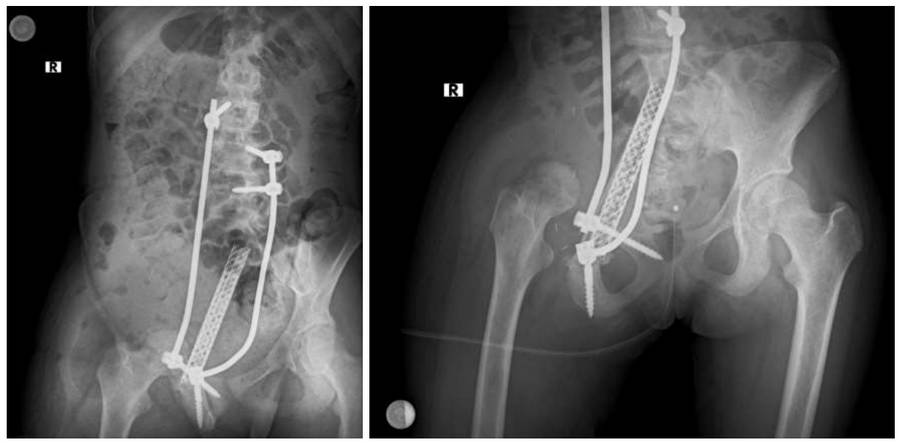

- The patient, who had no metastases detected in the scans, underwent reconstruction with rod/screw+titanium cage+fibula after lumbo-sacro-pelvic resection.

Post-surgery: The X-ray shows the reconstruction procedure after resection.